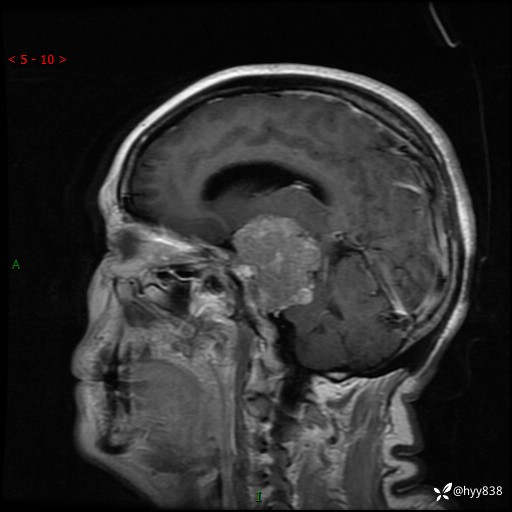

颅脑MRI平扫+增强